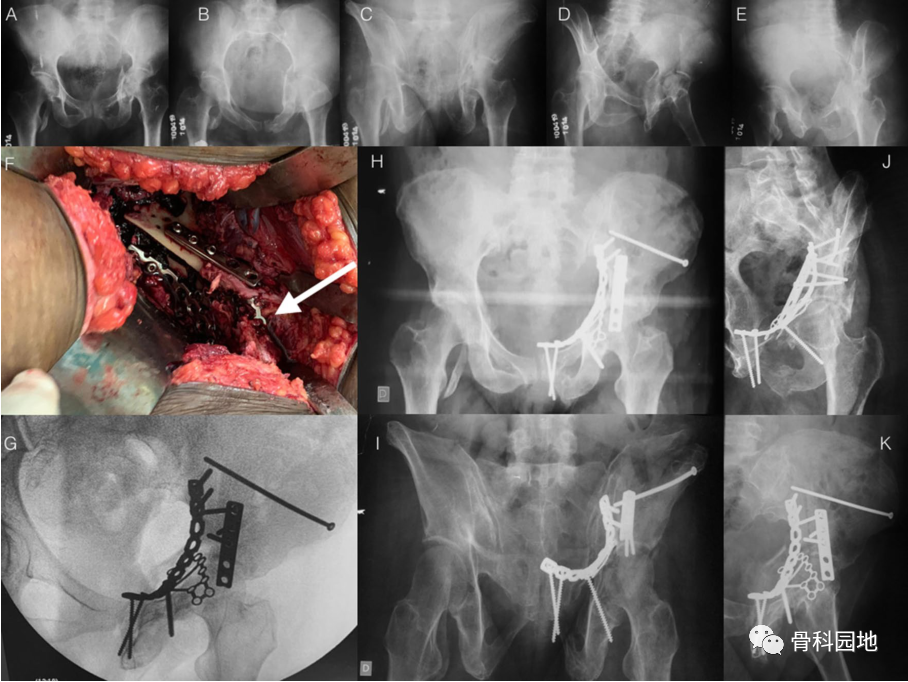

一、髂骨翼骨折

绝大多数髂骨翼骨折可以保守治疗。然而,在某些情况下,骨折粉碎和移位可能相当大,导致严重的髂骨翼畸形。传统植入物无法提供足够的覆盖区域,跟骨板可容纳粉碎性髂骨翼骨折,从而恢复原来的髂骨轮廓。

双侧粉碎性髂骨骨折的示意图。观察单个跟骨板与使用 2 个传统重建板的同一区域的封闭区域。即使有2个重建板,覆盖面积也较小(左侧)

骨盆前后位 X 线片显示左侧股骨粗隆下骨折、右侧骶骨骨折、右侧耻骨支骨折和髂骨翼粉碎性骨折。左侧的跟骨板固定髂骨翼粉碎性骨折